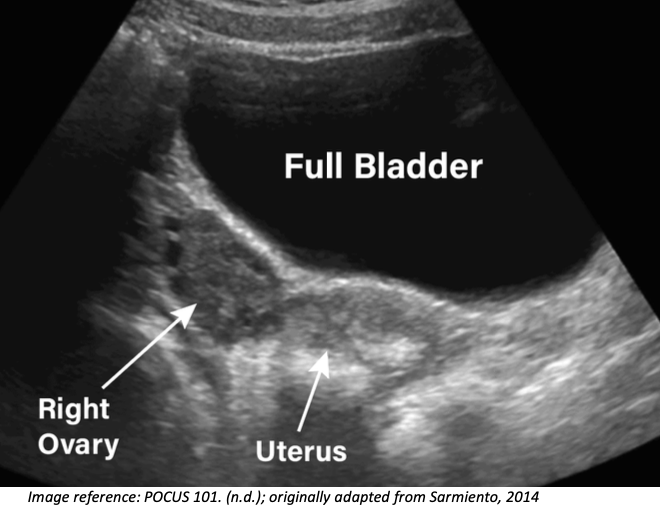

Appearance: Oval, isoechoic or mildly hypoechoic stroma with anechoic cystic follicles.

Location: Just lateral to the uterus and medial to the internal iliac vessels.

- The normal ovary will appear as an oval structure with an isoechoic, if not slightly hypoechoic stroma (the supportive connective tissue surrounding the follicles) and variable anechoic cystic follicles.

- The ovaries will appear just lateral to the uterus and medial to internal iliac vessels (Schwimer, 1985).

With the probe in the transverse position, gently rock the probe’s tail toward the patient’s left to bring the right ovary into view. It may require a little cephalocaudal sweeping to find the ovary.

To visualize the left ovary, use the same approach in the opposite direction by rocking the tail toward the patient’s right